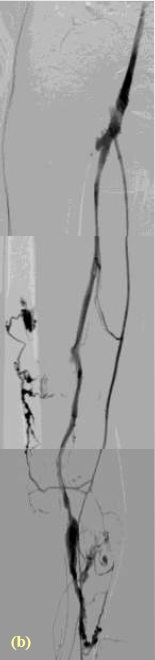

弥漫性静脉畸形

- 凝血状态 (急性弥漫性血管内凝血(+广泛静脉畸形 ≠ Kasabach-Merritt 综合征 )<3%。应该检查PT,APTT和纤维蛋白原等,但这些项目对于?(Giant extratruncular lesions), 深静脉血栓形成(deep venous thrombosis),大的边缘静脉( large marginal vein)不列为常规检查。静脉石病变也不是这类检查的适应症。 Tissular 静脉畸形治疗的适应症包括